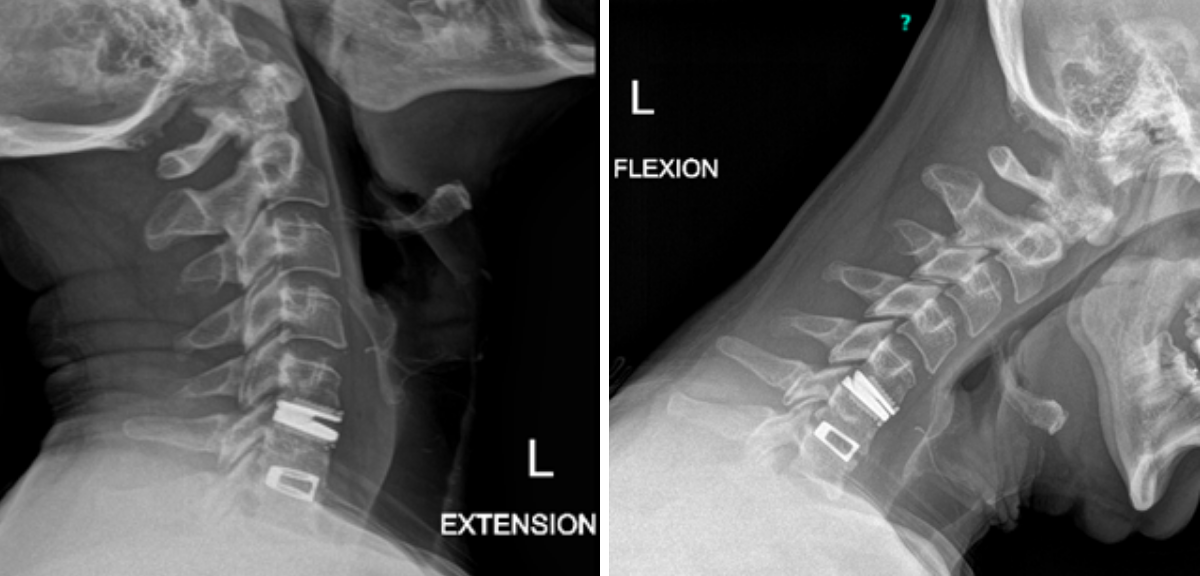

Figure 4.

Catheter angiography prior to angioplasty revealed critical stenosis (Figure 2). Angioplasty was therefore performed under local anesthesia with an embolic protection device deployed to catch any dislodged debris (Figure 3). After angioplasty, a stent was opened across the lesion to maintain long-term patency (Figure 4). Post-stent angiography showed smooth dilatation of the lesion. The patient’s aphasia continued to improve at his 6-week follow-up visit and duplex revealed no significant stenosis through the stent.